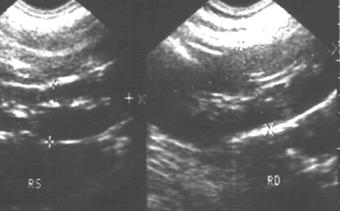

| Рис. 6.15. Сонограмма почек. Увеличение паренхимы правой почки (26 мм, двойная стрелка) и снижение ее эхогенности. Острый пиелонефрит правой почки. |

| Рис. 6. 16. Радиоренограмма с 131I-гиппураном. Кривые над почками. Левая почка − норма. Нарушение секреторной и экскреторной функции правой почки. Острый пиелонефрит правой почки. |